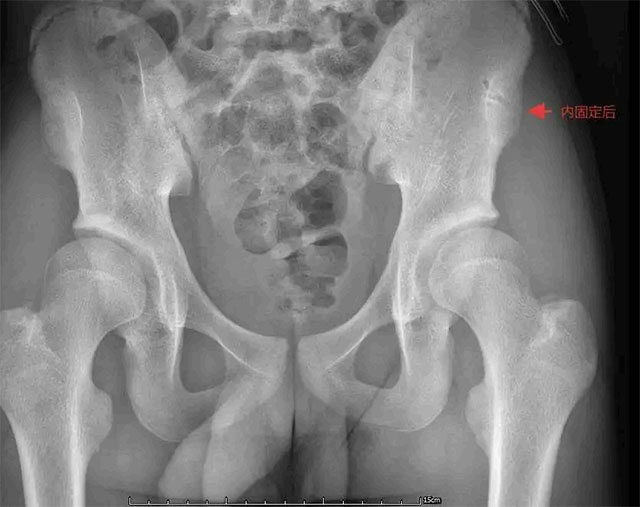

针对青少年生理特点与运动需求,科室制定个性化治疗方案。对于骨折移位超1cm、关节功能受限或运动需求高的患者,优先采用微创切开复位内固定术——仅2-3cm的微创切口,沿髂嵴精准切开避开神经,最大程度减少组织损伤,再根据骨折情况用空心螺钉等方式坚强固定。

伤后1周内是手术黄金期,此时肿胀消退、解剖清晰,复位更顺利,还能为早期康复创造条件。

术后分阶段康复同样关键,0-2周制动休息配合基础训练防并发症;2-6周逐步屈伸髋膝、尝试部分负重;6周后强化肌力与平衡训练,通常3-4个月即可重返赛场。